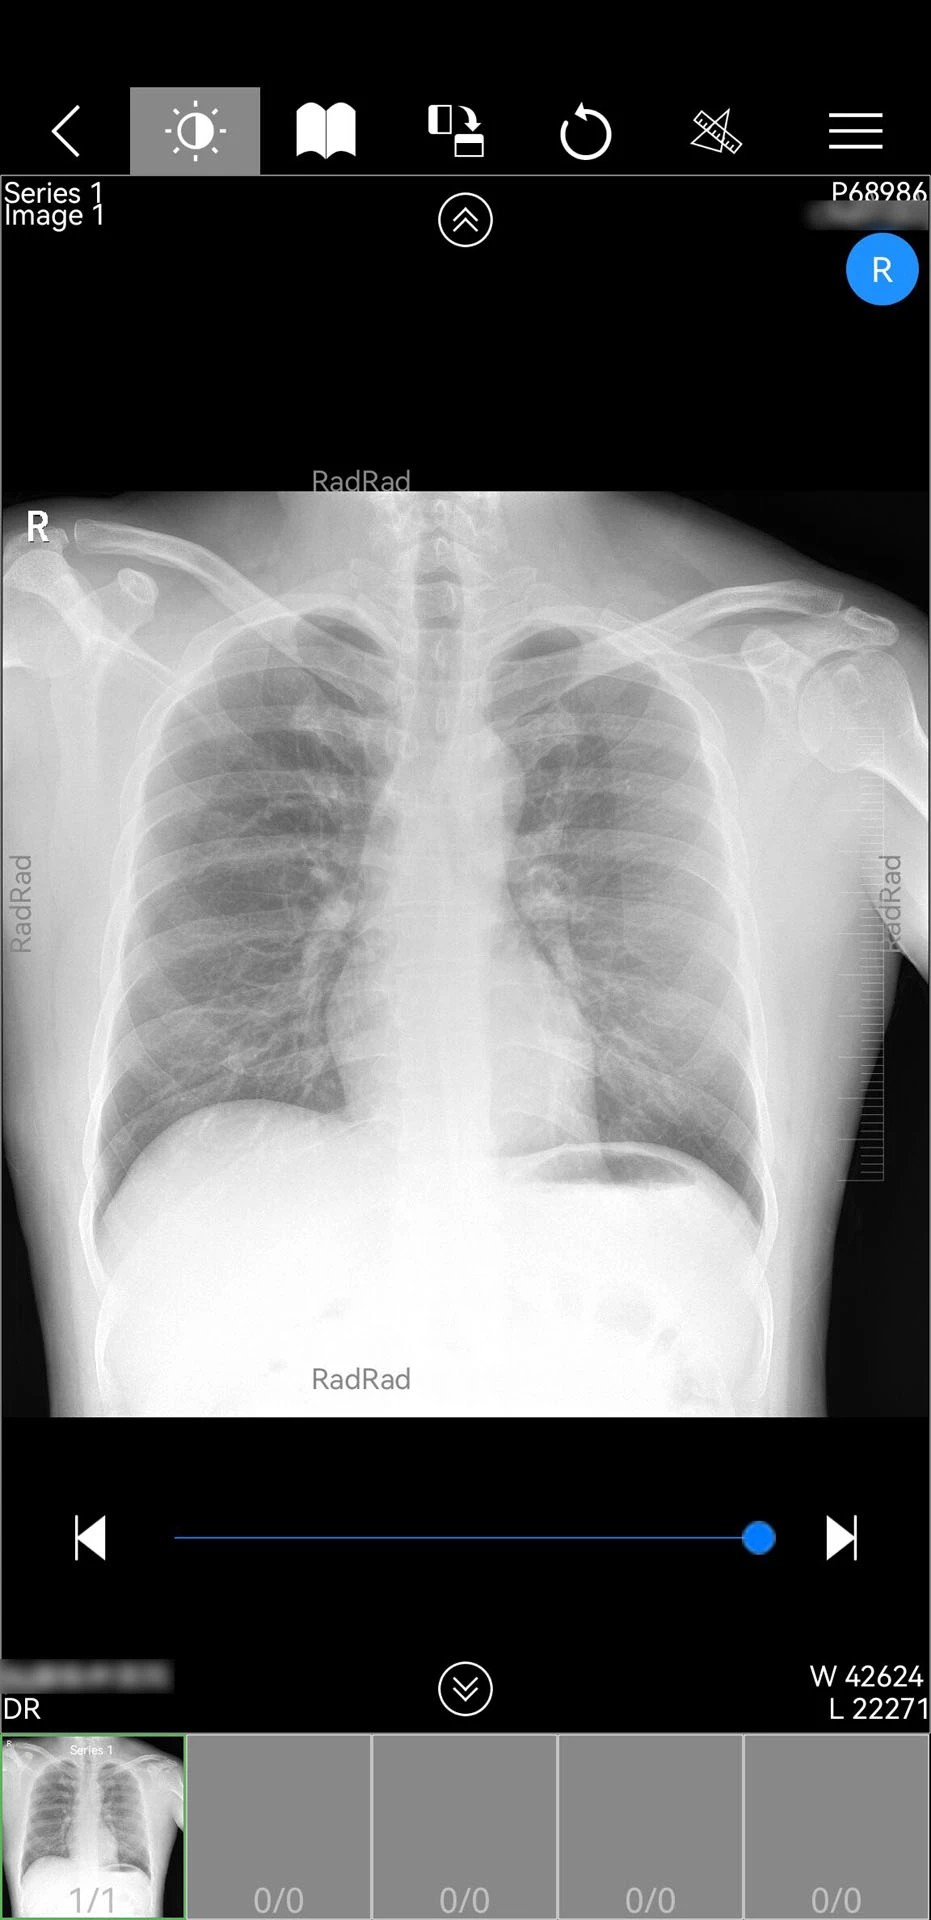

1. 多模态影像调阅:支持CT、MRI、X光等医学影像的实时查看,并新增CT三维处理服务,医生可通过手机端对影像进行多角度旋转、缩放及三维重建,辅助精准诊断。例如,在骨科病例中,三维重建功能可清晰呈现骨折断端形态,为手术方案制定提供关键依据。

3. AI辅助诊断:集成智能分析模块,可自动识别影像中的异常区域并标注疑似病变。例如,在肺结节筛查中,AI算法可标记直径≥3mm的结节,并计算其体积、密度等参数,为医生提供量化参考。